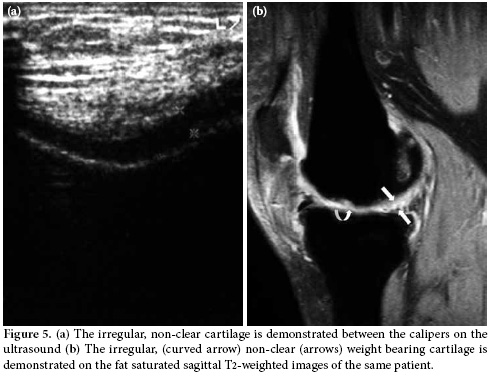

The US examination was performed first with the patient in a supine position in which the knee is flexed approximately 20-30 degrees while supported by a pillow, and the transducer was positioned longitudinally above the patella at the level of suprapatellar recess. The total synovial thickness and anteroposterior diameter of the suprapatellar bursa were measured. The synovial proliferation was considered positive when the total synovial thickness was above 3 mm, and the effusion was considered positive when it was 5 mm or higher (Figure 1a, b). During the longitudinal scan at the level of the suprapatellar recess, special attention was paid not to compress the recess. In the evaluation of the synovial proliferation, any presence of vascularization as a supporting evidence was evaluated with the color mode of the power Doppler US (Figure 2). However, because the study aimed to compare the B mode US findings and MRI findings and no contrast material was used in the MRI evaluations, spectral analyses and/or comparisons could not be made. In the same position, the patellar and quadriceps tendons were examined, and tendonitis was diagnosed if the thickness was increased and blurring and heterogeneous hypoechogenecity were differentiated.

In the second position, the weight bearing medial and lateral femoral condylar cartilage thickness and clarity were evaluated with the knee in maximum flexion. The femoral condylar cartilage was measured on the weight-bearing area approximately 1.5 cm away from the intercondylar notch (Figure 3). The cartilage morphology was assessed using a scale: 1 for regular-clear (Figure 4a, b) and 0 for irregular, non-clear (Figure 5a, b). Finally, all the patients were evaluated for popliteal cysts with the knee extended in a prone position, and any presence of popliteal cysts was recorded.